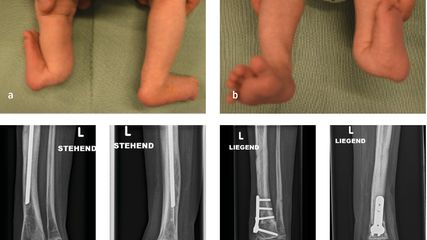

Anhand der klinischen Zeichen und der Symptomdauer unterscheidet man zwischen akuter und chronischer PPI. Die akute PPI ist durch eine kurze Symptomdauer (<3 Wochen) charakterisiert. Sie tritt entweder in der frühen (<4 Wochen) Phase nach endoprothetischem Gelenkersatz (akute postoperative PPI) oder aber verzögert (>4 Wochen, ggf. erst mehrere Jahre) nach Endoprothesenimplantation im Rahmen einer hämatogenen Streuung eines endoprothesenfernen Infektionsherdes (akute hämatogene PPI) auf. Typischerweise imponieren hier lokale Infektionszeichen wie Schmerzen, Schwellung, Rötung, Überwärmung oder eine prolongierte Wundsekretion (>7 Tage). Die Unterscheidung zwischen akuter und chronischer PPI basiert auf den Eigenschaften des bakteriellen Biofilms. Beim Vorliegen einer akuten PPI ist von einem unreifen bakteriellen Biofilm auf der Endoprothesenoberfläche auszugehen. Bei der chronischen PPI (>4 Wochen postoperativ) mit längerer Symptomdauer (>3 Wochen) liegt hingegen ein potenziell reifer Biofilm vor. Die klinischen Symptome sind in der Regel weniger ausgeprägt. Jedoch kann das Vorliegen einer kutanen Fistel oder von radiologischen Zeichen der Endoprothesenlockerung auf eine chronische Infektion hinweisen (z. B. Abb. 1).

Abb. 1: Patient mit chronischer Hüftendoprotheseninfektion. Radiologisch zeigen sich infektionsbedingte periprothetische Osteolysen (*, a) und klinisch imponiert eine kutane Fistel (b).